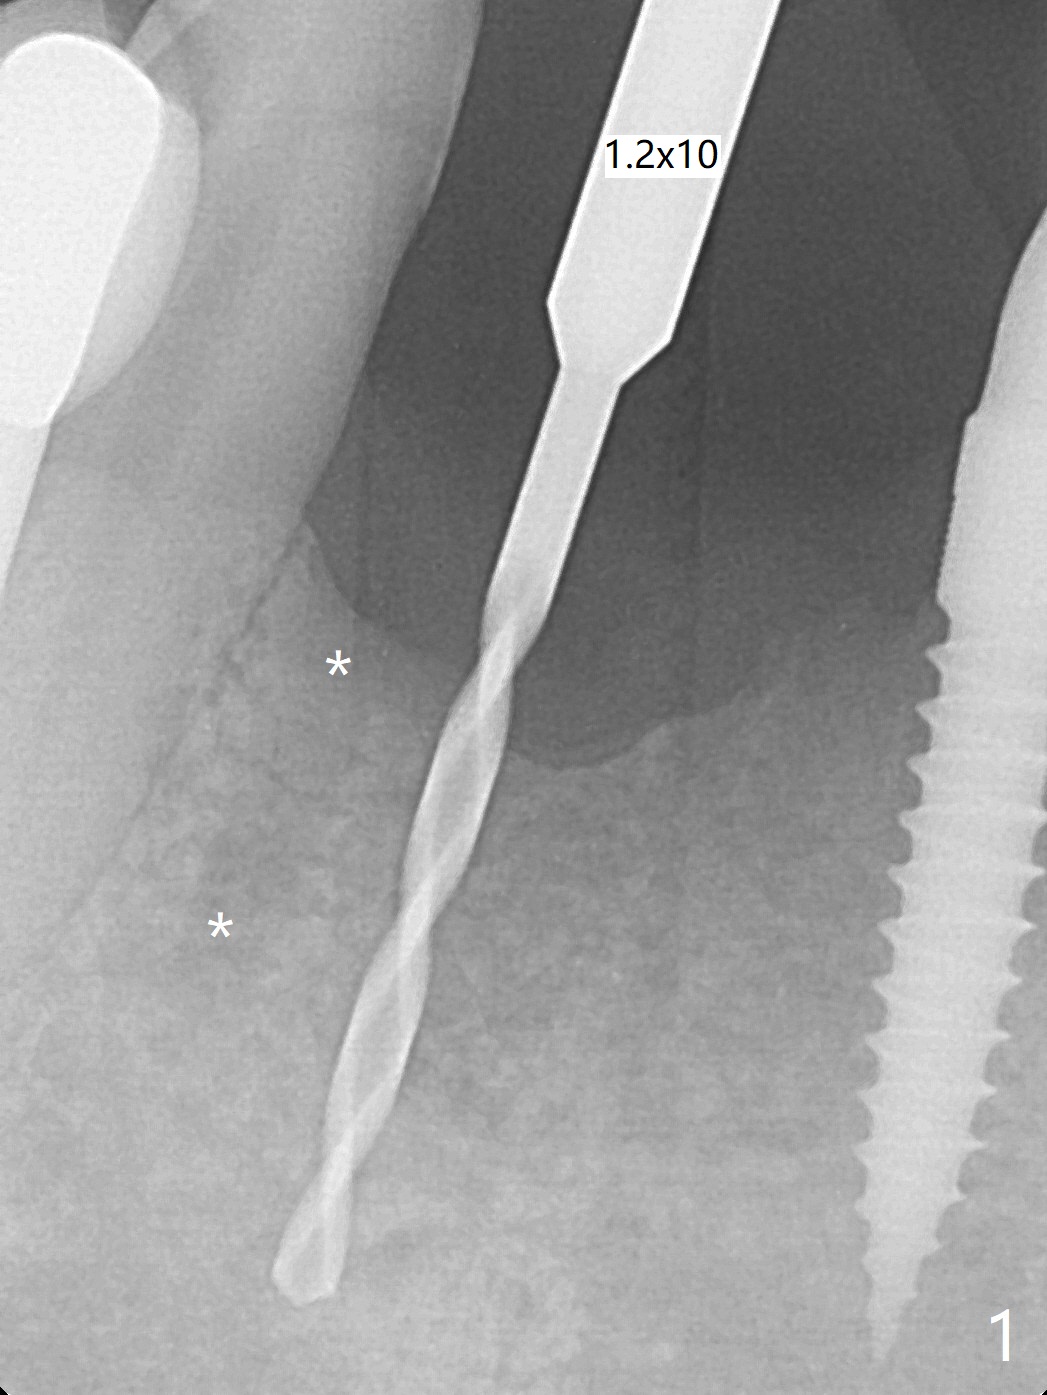

After removing #23-26 FPD and the 3x14 mm 1-piece implant at #26 (Fig.1,2 *), a new osteotomy is initiated in the narrow ridge (after ridge top reduction) approximately at #25 (Fig.2 <). Following placement a 2x10(4) mm implant at #25 (Fig.3-5) and Osteogen plug in the osteotomy at #26, Vanilla graft is placed around the implant, especially buccal. Periodontal dressing is applied after suturing. The buccal and lingual flaps are erythermatous and edematous without pain 8 days postop (Fig.6). The wound seems to be healing 2 weeks postop (Fig.7), no sign of osteonecrosis. With placement of a 2 mm implant at #25 (Fig.8 (>: bone graft buccally)), the buccal plate remains normal in thickness. When a 3 mm implant is placed at #23 (Fig.9), approximately 4 threads appear to be exposed (between arrowheads), partially due to the thick lingual plate (*).